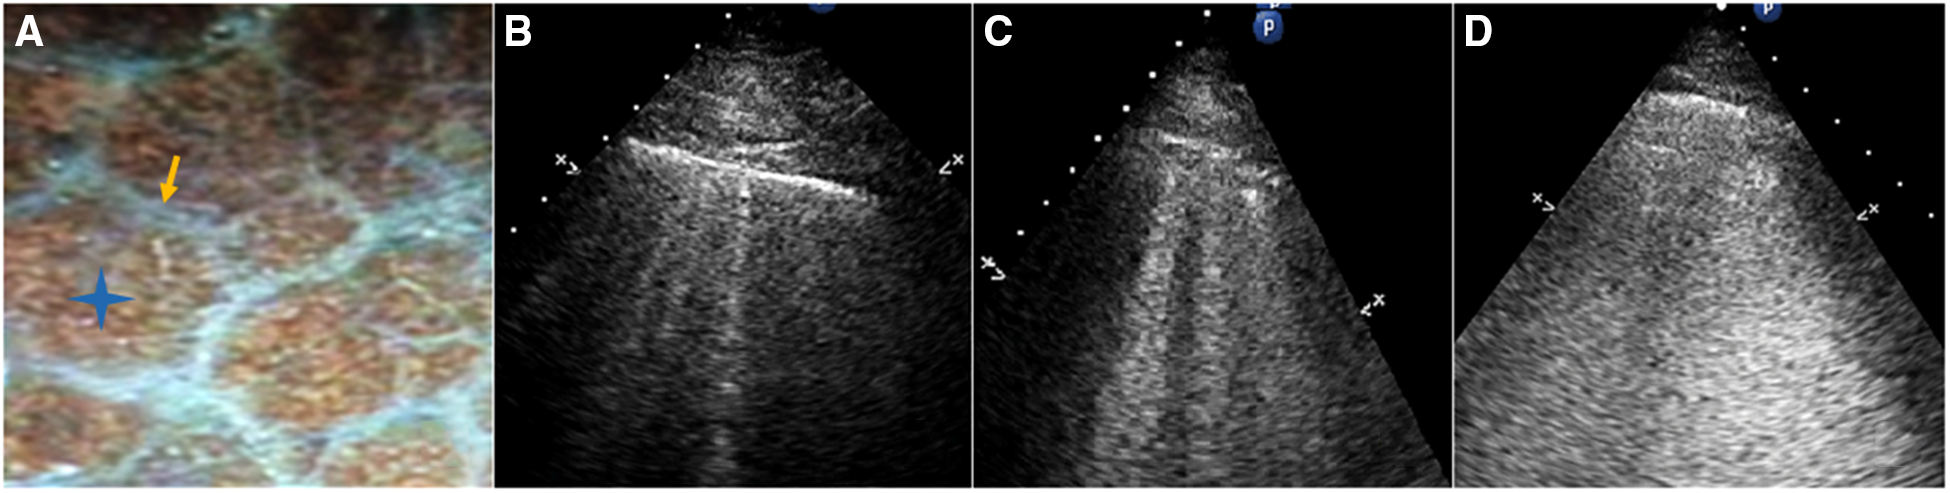

The following B-line scoring method was used: The anterior and lateral chest wall was divided into seven-zones. B-line score was then calculated according to the degree of pulmonary edema (Figure 3). A score of 0 (zero) was defined as absence of B-lines. A score of 1 corresponded to septal syndrome (B-lines at regular distances, corresponding to pleural projection of the subpleural septa, at approximately 7 mm distance). Interstitial-alveolar syndrome was assigned a score of 2 (B-lines more confluent, separated by <7 mm). A score of 3 referred to white lung (B-lines coalesced, confluent B-lines >80%, resulting in an almost completely white image). Images with the highest score in each zone were recorded. A final ultrasound B-lines score was obtained by summing the B-lines scores of the seven zones of anterolateral chest scan (3).

Figure 3

(A) Gross anatomy of the lung surface: the white line pointed by the yellow arrow is the subpleural interlobular septum which is approximately 7 mm apart. The blue star indicates the location of the alveoli. (B) Septal syndrome: B-lines are approximately 7 mm apart, corresponding to subpleural interlobular septa. (C) Interstitial-alveolar syndrome: B-lines are confluent. (D) White lung. B-lines have coalesced, resulting in an almost completely white echographic image.